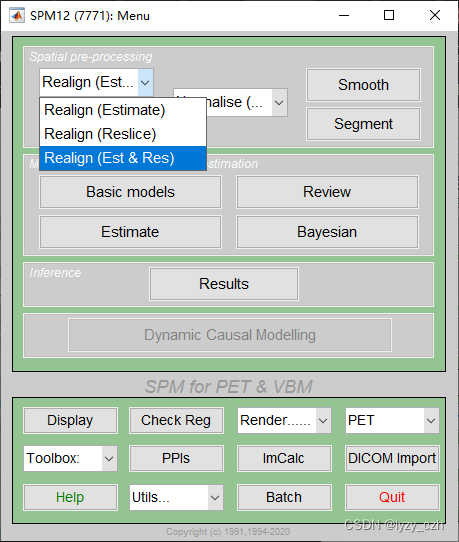

2) Realign,只需要编辑Session,其他参数不用改,编辑好后点击左上角绿色三角形按钮: